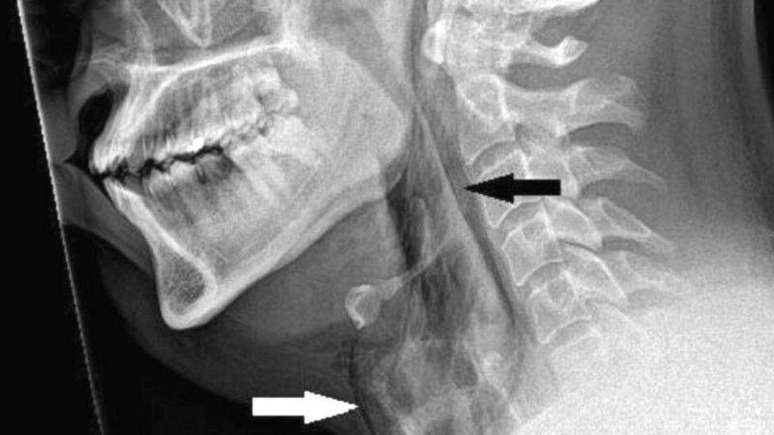

Paciente teve ruptura de 2 mm na traqueia

Foto: BMJ / BBC News Brasil

Os exames revelaram que ele sofreu uma ruptura de 2 mm na traqueia.

No novo caso relatado, médicos examinaram o paciente e ouviram um estalo ao tocar seu pescoço.